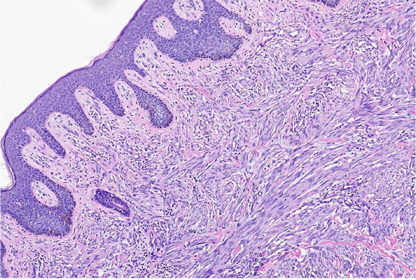

低倍镜下,肿瘤位于真皮层及皮下,肿瘤主要由梭形细胞构成,含有少量卵圆形细胞,部分区细胞丰富,部分区细胞较稀疏,梭形细胞排列成编织状、束状及旋涡状(图1A)。肿瘤细胞与周围组织呈交错浸润性生长,局部呈膨胀性/推挤性生长。肿瘤内薄壁血管较丰富,呈分支状,管腔开放,局部可见少量淋巴细胞浸润(图1B)。肿瘤细胞累及脂肪及皮肤附属器,部分区间质可见黏液水肿/变性及纤维胶原增生(图1C)。

高倍镜下,细胞核呈长/短梭形或卵圆形,染色质细腻/开放,核膜光滑,可见细小核仁。胞浆嗜伊红,较丰富,核浆比尚可。偶见多形性细胞和多核细胞,偶可见核分裂象(热点区约1个/10HPF)(图1D),未见肿瘤性坏死及病理性核分裂。根据FNCLCC分级,肿瘤细胞的形态符合低级别。

组织形态学上,5例局限于真皮,3例肿瘤主体位于皮下(真皮深层受累有限)。肿瘤细胞由梭形细胞及卵圆形细胞组成,交叉、束状生长或无规律排列;大部分肿瘤细胞异型性小,染色质细腻,细胞质轻-中度嗜酸性,细胞边界不清;这部分肿瘤细胞形态温和,核分裂少见(<1个/10 HPF),符合低级别肿瘤形态。部分区间质胶原化及黏液变性,肿瘤含有线性-分支状薄壁血管,肿瘤周边呈浸润性/交错性边界。部分肿瘤细胞可呈上皮样形态,个别病例表现出肿瘤细胞核局灶的多形性,肿瘤性坏死范围不等,一般较少见;然而,也有少量区域可表现为核分裂象活跃及灶性坏死,形态学符合中级别肉瘤[1]。大部分肿瘤伴有少-中等量淋巴细胞浸润,也可见弥漫散在的淋巴细胞浸润/积聚,类似炎症性肌纤维母细胞瘤(IMT)。肿瘤细胞均显示出免疫组化弥漫性ALK(D5F3克隆)的阳性表达。其中7例弥漫性共表达CD34和S100蛋白,另外1例只表达CD34,但不表达S100蛋白。所有病例的肿瘤细胞EMA、AE1/AE3、和SOX10均为阴性。分子检测中,通过一代测序(NGS)及RT-PCR(ARMS方法)检测到PLEKHH2:ALK融合或EML4:ALK融合[1]。文献中的病例与本例形态学及分子改变具有高度重叠性。